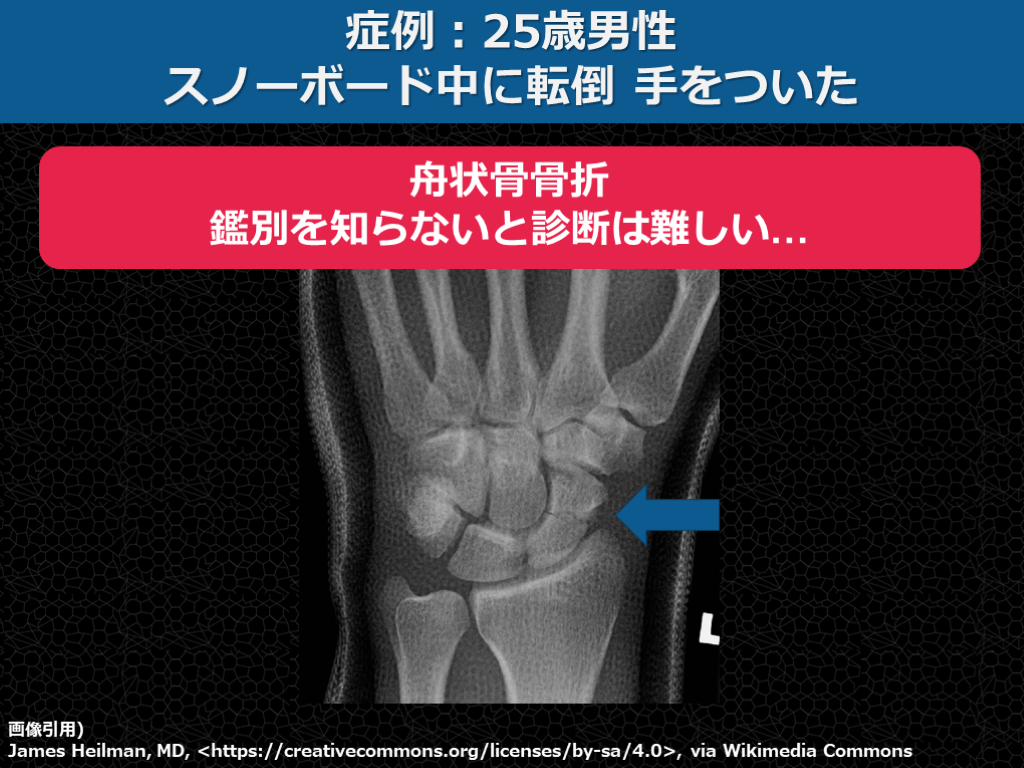

症例:25歳男性 スノーボード中に転倒 手をついた 画像引用) James Heilman, MD, <https://creativecommons.org/licenses/by-sa/4.0>, via Wikimedia Commons

症例:25歳男性 スノーボード中に転倒 手をついた 画像引用) James Heilman, MD, <https://creativecommons.org/licenses/by-sa/4.0>, via Wikimedia Commons 舟状骨骨折 鑑別を知らないと診断は難しい…

①年齢×受傷機転で鑑別を想起 参考に作成)増井伸⾼ 著 2019 ⾻折ハンター 中外医学社 ※FOOSH: fall on outstretched hand   覚えて鑑別のレパートリーを増やす →知らない骨折は見抜けない!